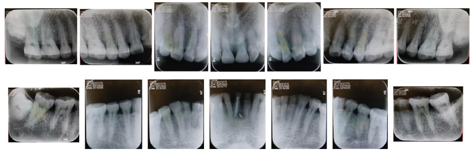

结合病史、口内检查、X线片诊断为上下颌牙列重度磨耗。

17-47重度磨耗至牙本质深层,探无不适,叩痛(-),未及明显松动,牙龈无明显异常,牙髓活力正常;

41可见牙色充填体,X线片示:根充恰填,根尖周病变范围较治疗前缩小。

17-47重度磨耗

本病例中,患者全牙列重度磨耗,垂直距离丧失,但牙体组织的缺损主要位于咬合面,且患者无明显疼痛不适症状,牙周情况良好,牙髓活力正常,X线片未及明显根尖周病变及牙槽骨吸收。这种情况若使用全冠进行修复需要去除约70%的牙体硬组织,既增大了出现牙髓并发症的风险,又使基牙抗力减小,不利于修复体的长期稳定[2]。对于此类因磨耗导致咬合面硬组织缺损、牙髓活力正常,需要重建咬合面形态的患牙,使用